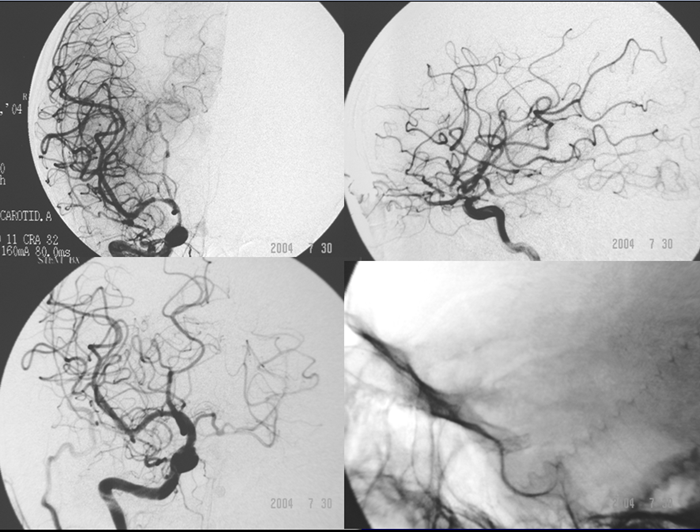

反复TIA或中风,经正规药物预防无效,无严重神经功能障碍。

无症状者,狭窄>70%;有症状者,狭窄> 50%;TCD显示远段低波动性(PI指数小于0.4); 由SPECT/PWMRI/PET其中之一证实局部相关脑组织缺血。